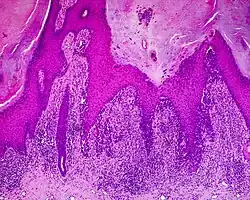

Histology

The main characteristic of acral lentiginous melanoma is continuous proliferation of atypical melanocytes at the dermoepidermal junction.[15] Other histological signs of acral lentiginous melanoma include dermal invasion and desmoplasia.[16]

According to Scolyer et al.,[17] ALM "is usually characterized in its earliest recognisable form as single atypical melanocytes scattered along the junctional epidermal layer".

Acral lentiginous melanoma (ALM)